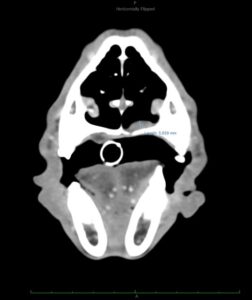

Dos semanas más tarde se realiza el TC de reestadiaje y se detecta la presencia de enfermedad metastásica en pulmón. Adicionalmente, la afectación completa del paladar y la invasión en cavidad nasal hacen que se descarte la cirugía como terapia local.

En el momento del estadiaje inicial, el paciente presenta un buen estado general, pero se evidencia el crecimiento de la lesión primaria y la existencia de metástasis regionales y a distancia según TC. Se administra la segunda dosis de la vacuna de melanoma y se planifica radioterapia paliativa, seguida de quimioterapia adyuvante con carboplatino. Cuatro semanas más tarde se completa la radioterapia paliativa en cinco sesiones (22.5Gy) dirigida al melanoma oral y metástasis en ganglios linfáticos mandibulares y retrofaríngeos bilaterales. Los cuidadores rechazan finalmente el tratamiento con carboplatino adyuvante.

A los 18 meses del diagnóstico, los cuidadores refieren la aparición de hifema y exoftalmia en el ojo derecho, lo que sugiere metástasis, además de una masa perianal compatible con neoplasia indiferenciada (posible melanoma amelanótico). En el estudio de TC se documenta una respuesta completa de la lesión primaria y metástasis nodales y una remisión casi completa de las metástasis pulmonares (lesiones milimétricas equívocas) (imagen 1). Se realiza la resección de la masa perianal, pero los cuidadores rechazan la enucleación.

A los 28 meses se realiza un TC de re-estadiaje antes de considerar el segundo protocolo de radioterapia, donde se documenta una progresión objetiva de la masa oral y ligera progresión de la metástasis pulmonar (imagen 1).